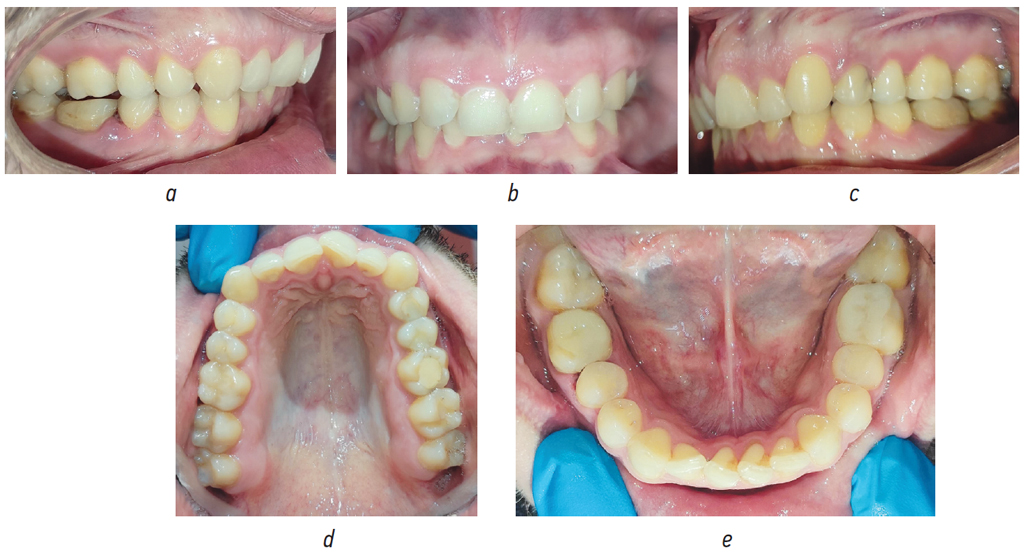

Пациент Ч., 30 лет (рис. 1, 2), и пациентка Ж., 25 лет (рис. 3, 4), обратились в клинику с жалобами на неровное положение зубов, заднее положение подбородка. В результате осмотра у обоих выявлено дистальное соотношение зубных рядов, глубокий прикус, тесное положение зубов легкой степени, увеличение выпуклости лицевого профиля и лица, уменьшение нижней трети лица, у пациентки Ж. — смещение подбородка влево.

Рис. 4. Зубные ряды пациентки Ж. до лечения в боковых (а, c), прямой (b), окклюзионных (d, e) проекциях

Fig. 4. Dental rows of patient Zh. before treatment in lateral (a, c), straight (b), and occlusal (d, e) projections